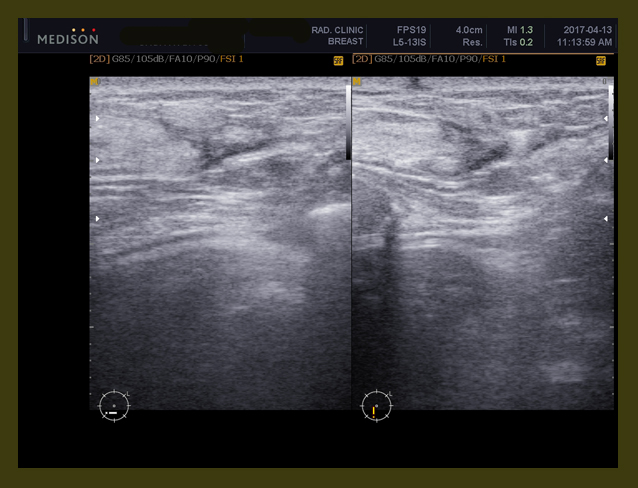

유방초음파

1. left lower inner quadrant와 right upper outer quadrant의 유방암을 수술한 병력이 있고

2. 불균질하고 뾰족한 경계를 가지는 저음영의 부분이 RUOQ(우측 상방바깥쪽면-right upper outer quadrant)에 보이는데 이는 수술 후의 섬유화된 흔적으로 보인다.

3. 선과 같은 액상의(cystic) 7mm 크기의 동그란 근육 내의 결절이 이전 수술부위인 좌측하부내쪽 1/4 부위에 보이는데 이는 수술 후의 흔적일 수도 있고  종양이 다 제거되지 않고 남아있을 가능성도 있다.

골반초음파

1. 6.8cm x 5.9cm x 8.1 cm 크기의 여러 개로 갈라진 격벽을 가지고 있는 액상의 부위가 왼쪽 자궁주위 조직에 보이는데 양성의 혹으로 보인다.

2. 자궁내막의 비후가 관찰된다.

3. 약 3cm 크기의 근종으로 의심되는 부분이 자궁의 아래쪽에 보인다.